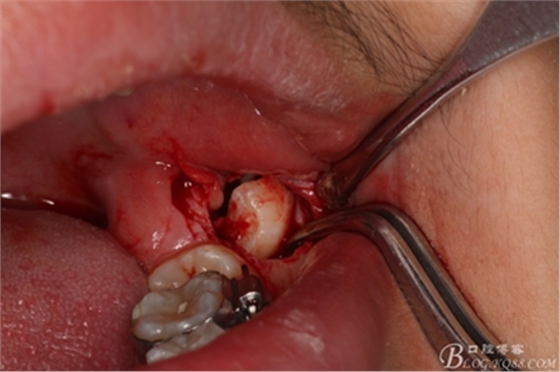

圖12.縱分完成的牙冠

圖13.牙挺放入分開的牙縫之間

圖14.先取出遠(yuǎn)中部分。